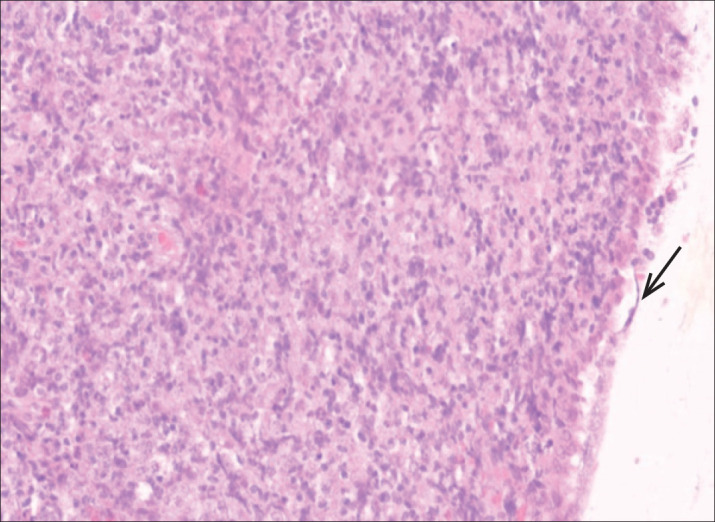

Background: Burkitt's lymphoma (BL)belongs to the group of lymphomas with an aggressive clinical course. It is a rare form of lymphoma in adults with an incidence of 1200 patients per year in the USA.

Objective: The aim of this article was to present for the first time the case of a patient in whom Burkitt's lymphoma was proven by biopsy and curettage of the uterus, and at the same time in the biopsy of palatine tonsil and bone.

Case report: A 64-year-old female patient who comes because of difficulty in swallowing, enlarged neck lymph nodes and vaginal bleeding. Under diagnosis Lymphoma non Hodgkin Burkitt CS IV B, ECOG 3, IPI 5 (high risk), R-IPI:5 (poor prognostic index) introduction of IHT R-CHOP 4 cycles with therapeutic response.